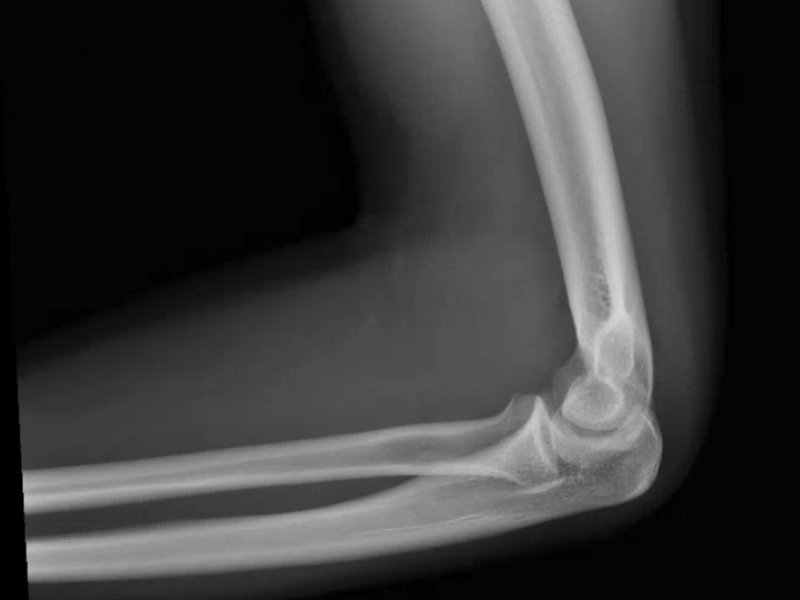

What's the Diagnosis? By Dr. Michael Tom

A 19 yo M presents to the ED complaining of elbow pain after